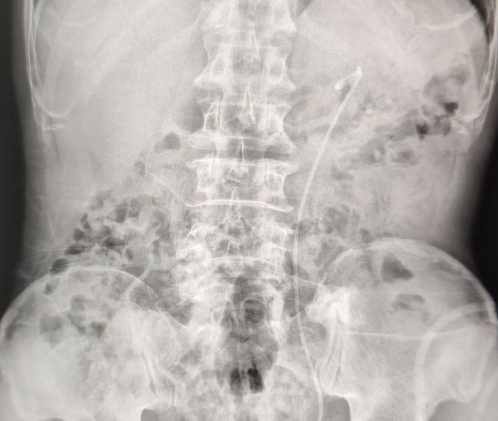

三期手术则通过输尿管软镜对残留小结石进行彻底清理,避免后续梗阻风险。

经过三期精细手术,潘大叔左肾结石被完全取净,康复情况良好。

三期手术后检查显示已完全取净结石